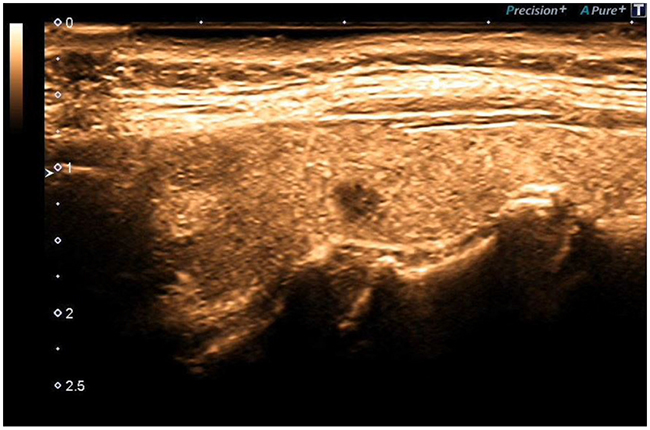

The ADF (Advanced Dynamic Flow) allows to underline the vessel flow of the newly formed tortuous vessels [14].

ADF test showed a clear flow through newly formed tortuous vessels at the periphery of the specific micro-focus (Figure 6, 7).

Figure 6: ADF, Advance Dynamic Flow.

Figure 7: ADF, Peripheral Microcirculation.

The ADF allowed detection of microvascularization at the periphery of the micro-focus with accuracy.